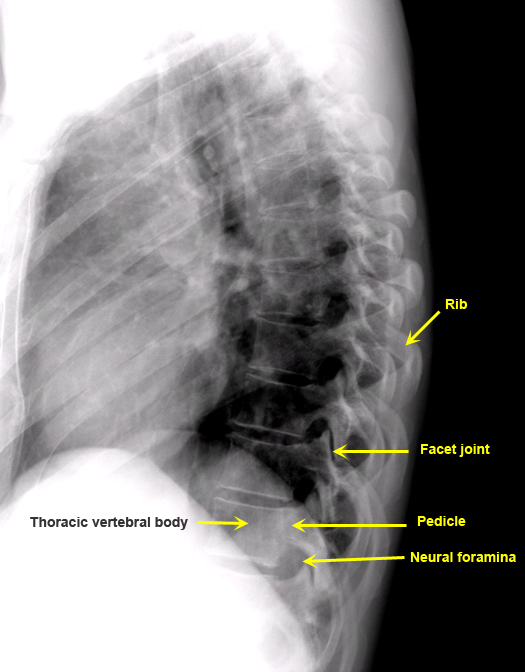

Plain Films of Skull and Spine